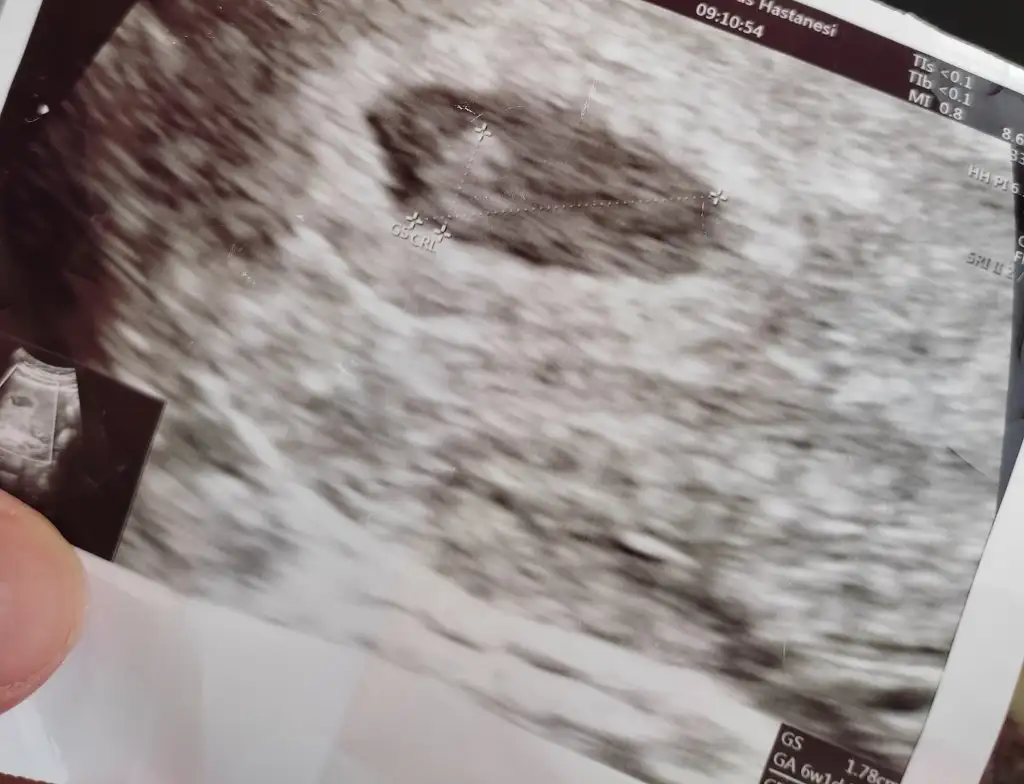

,6 haftalık canım ama duyduk keseyide çok erken görmüştüm

Ne güzelmiş ya, bize de beklemeler düştü :),6 haftalık canım ama duyduk keseyide çok erken görmüştüm

Ay maşallah ne güzel erken duymuşsunuz. Ses kaydı aldınız mıRegle göre 6+1 ama tüp bebekten hesaplayinca farklı 5. Gün embriyosu transfer edildi

Ses kaydim yok ama kese var canım atiyimAy maşallah ne güzel erken duymuşsunuz. Ses kaydı aldınız mıkese fotoğrafı var mı